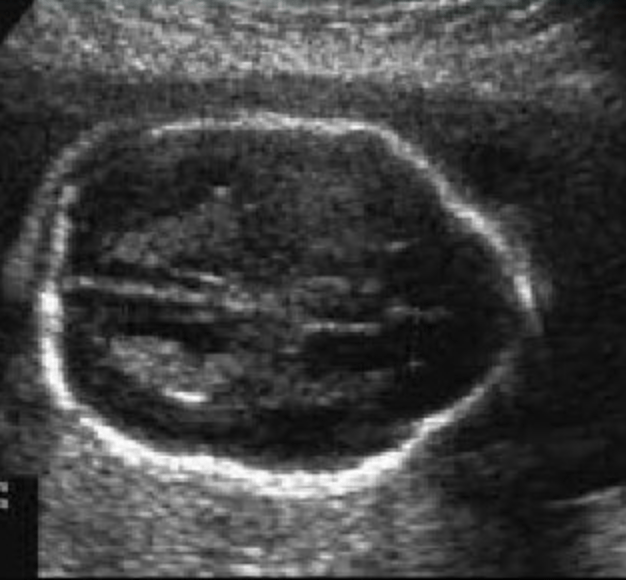

What is the condition?

Open neural tube defect

Aka Lemon sign